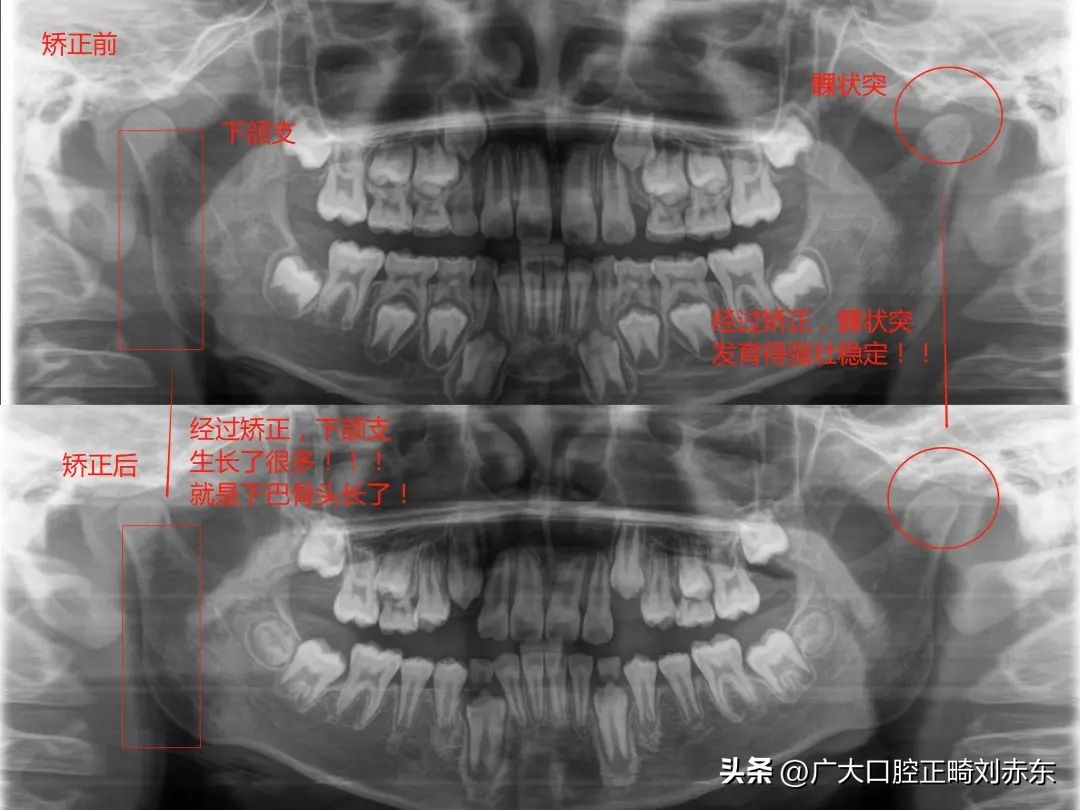

下颌后缩的最佳矫正时间

1、青春发育前期: 研究发现这类患者,如果不加干预,是会随着年龄增大越来越严重,如果下颌骨后缩是由牙齿咬合关系不佳造成,一般就可以在青春期的前期通过正畸方法进行矫正,此时机体刚好处于生长发育高峰期,下颌骨生长迅速,通过早期矫治,能够促进下颌骨有利生长。若错过最佳治疗时机,成年后可能需正颌手术治疗才能获得满意效果。